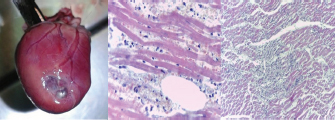

Some animals had histopathological alterations suggesting acute MI (areas of coagulative necrosis, with loss of striations, intracytoplasmic calcium deposition, increased acidophilia, and maintenance of tissular structure). In contrast, others evidenced signs of chronicity (areas of fibrosis, angiogenesis, mononuclear inflammation) (Fig. 2).

Fig. 1. Presence of marked myointimal hyperplasia (left) of an intromyocardiac coronary arteriole. Fatty transmural replacement of the free wall of the left ventricle (right). Both sections were stained with hematoxylin-eosin.

Fig. 2. Heart of a cat with a thinned area of the free wall of the left ventricle due to subendocardial infarction (left). Histopathological alterations compatible with acute myocardium infarction with polymorphonuclear infiltrations (middle). Changes suggesting chronic myocardium infarction with fibrosis areas distributed in a patchy pattern (right).